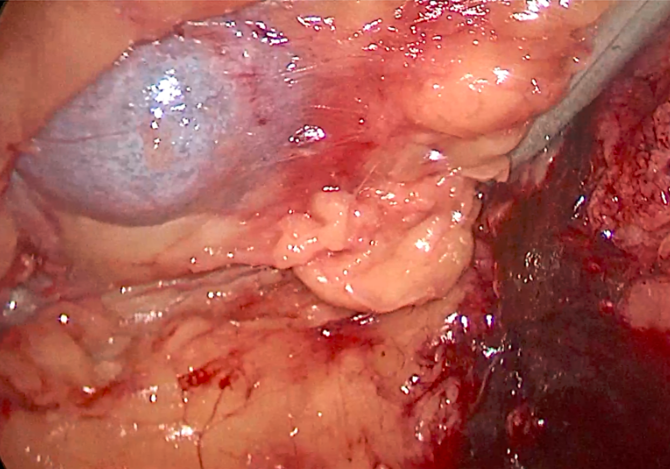

双侧输尿管切开取石术+双侧输尿管裁剪成型术,术中见上段输尿管因梗阻扩张似肠管,与周围脏器黏连明显,输尿管切开见结石周围包裹息肉,取石钳完整取出结石,双侧输尿管裁剪成型并留置内支架支撑。

正常人输尿管长约25cm左右,该患者输尿管迂曲扩张,长达35-40cm左右,裁剪部分输尿管成型